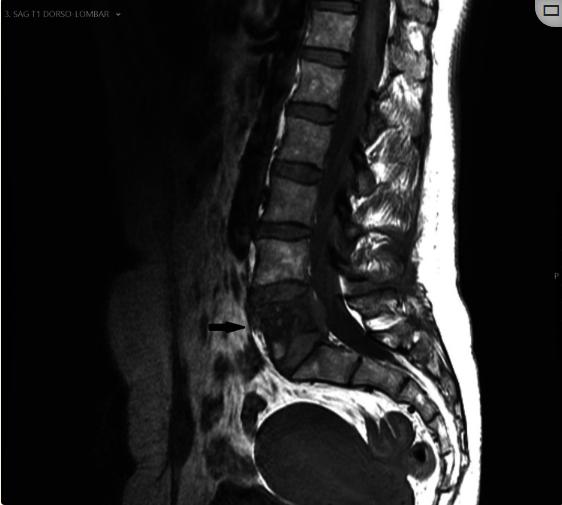

图3、磁共振成像,T1WI序列

在MRI上,病灶在T1WI上呈等信号